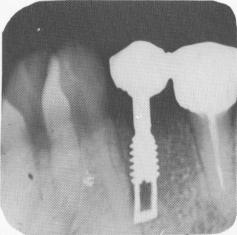

An interchangeable, serrated gold coping was placed over the implant post (Fig. 8-57). A loose mix of acrylic was placed inside the hollow ground pontic, the bridge seated, and the acrylic allowed to harden. The bridge was removed, with the gold coping as an integral part of the restoration (Fig. 8-58) . The excess acrylic was trimmed and polished. The bridge was cemented over the bicuspid tooth and implant post with hard cement (Fig. 8-59), and a final operative radiograph taken (Fig. 8-60).

Fig. 8-60. The postoperative radiograph.